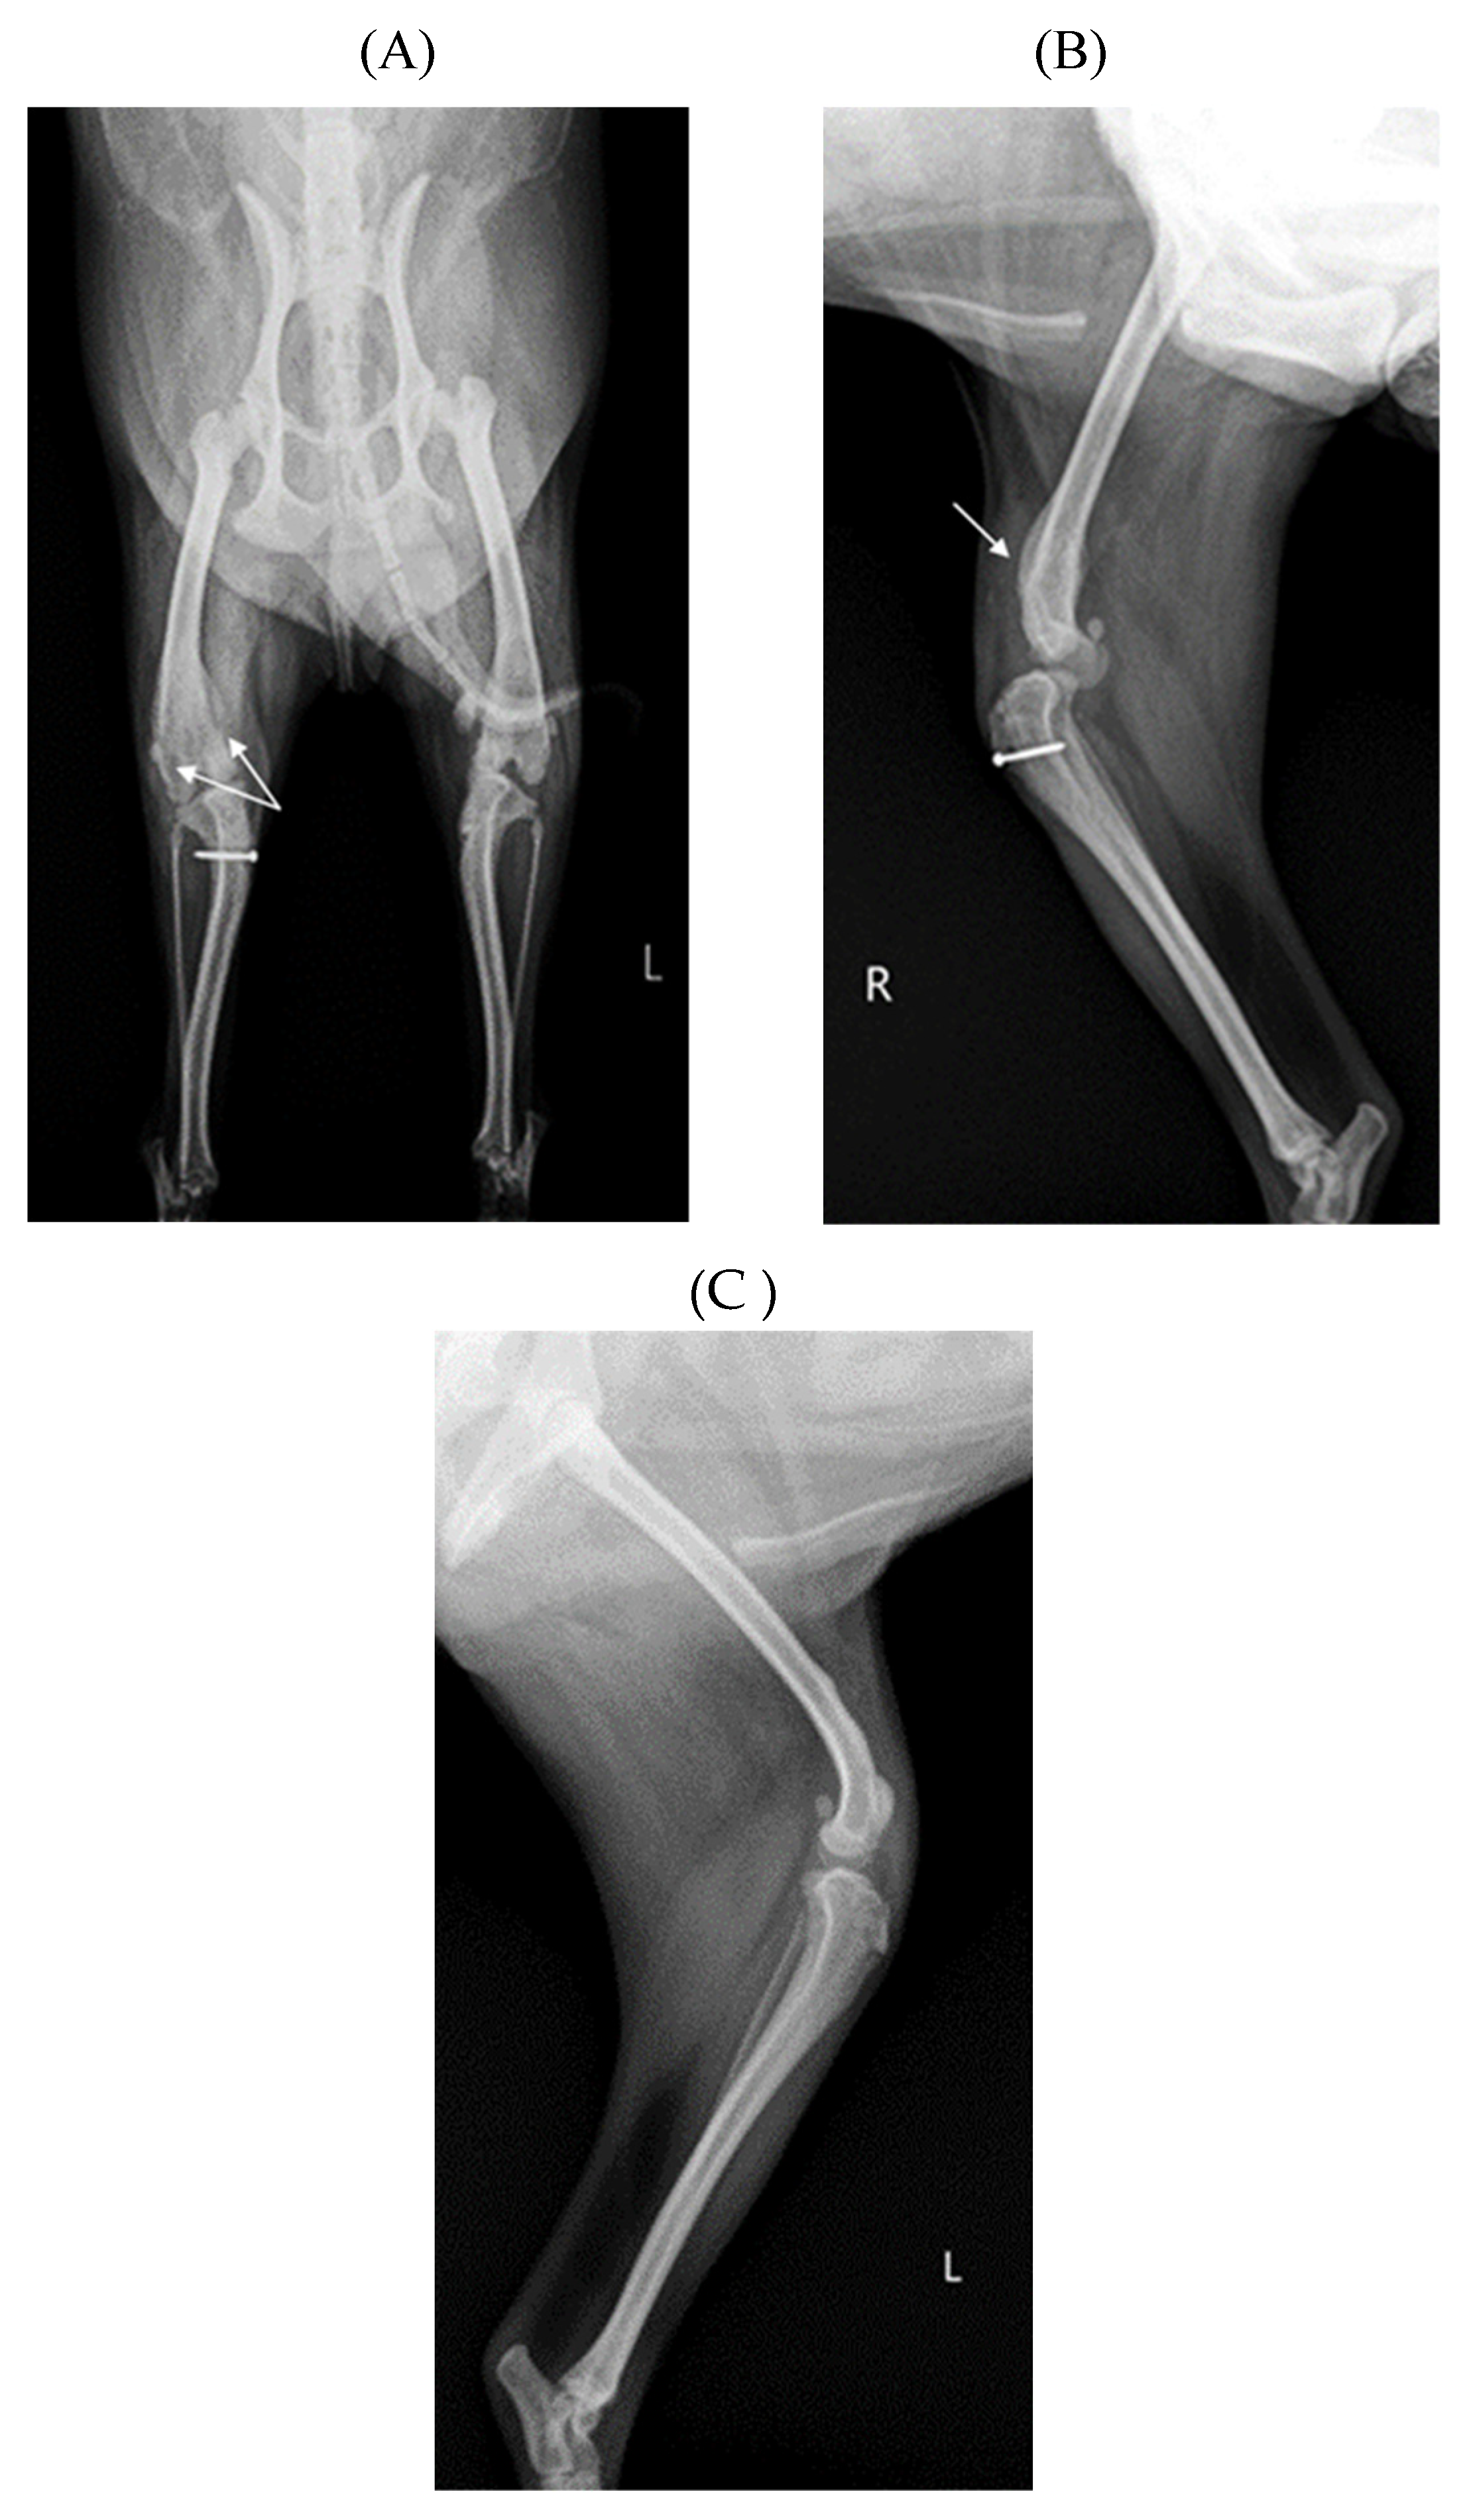

Before surgery, antibiotic and anti-inflammatory drugs were applied for about a month to relieve pain, edema and arthritis, and then the surgery was performed. For treatment, amoxicillin/clavulanic acid (Amocla, KUHNIL corp., 12.5 mg/kg) and carprofen (RIMADYL, Zoetis Inc., 2.2 mg/kg) were prescribed bid for 4 weeks. After one month, radiographic findings confirmed that inflammation and edema in both stifle joints were reduced (Figure 2). The owner was informed that stifle joint arthrodesis was to be performed on the right hind limb due to severe osteoarthritis, loss of the patella and rupturing of the cranial cruciate ligament, and that MPL correction was to be performed on the left leg, and the consent of the guardian was obtained.

Figure 2. Preoperative craniocaudal (A) and mediolateral (B, C) radiograph of the right and left stifle joints. Antiinflammatory drugs reduced pain, lower fever, and decrease in-flammation (swelling and damage) after the drugs applied for about a month. Arrow showed images with significantly reduced inflammation and edema compared to a month ago.